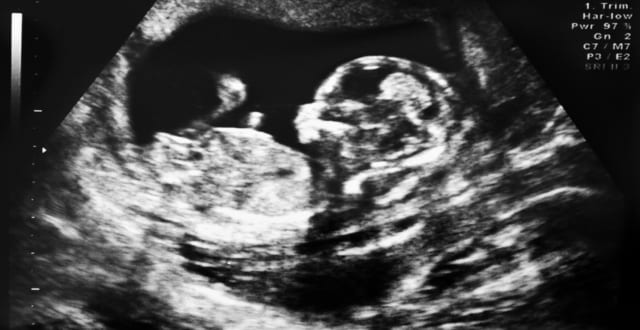

Entre as várias indicações e modelos de exames temos dois em especial que podem ser realizados durante a gravidez: o USG obstétrico e o USG obstétrico morfológico.

USG morfológico é um exame de ultrassom realizado durante o período gestacional, por médicos especializados e familiarizados com anatomia fetal. Os aparelhos para realização desse exame também são diferenciados.

Durante o primeiro trimestre a indicação para sua realização deve ser entre 11 e 14 semanas (quando o CCN 45 e 84 mm). Segundo a Fetal Medicine Foundation (FMF) o uso de variáveis como Idade Materna, Transluscência Nucal, presença de Osso Nasal e marcadores bioquímicos como PAPP-A e fração livre de βHCG são capazes de rastrear 95% das malformações. Importante aqui lembrar da diferença entre rastreamento e diagnóstico, o morfológico do primeiro trimestre ajuda muito no rastreamento (suspeita) de malformações, já que o diagnóstico definitivo se dará ao nascimento com o exame completo do concepto.

Já durante o segundo trimestre, temos outros objetivos a serem avaliados. Trata-se de um exame bastante complexo, sistemático e ordenado com objetivo de avaliar durante sua realização: